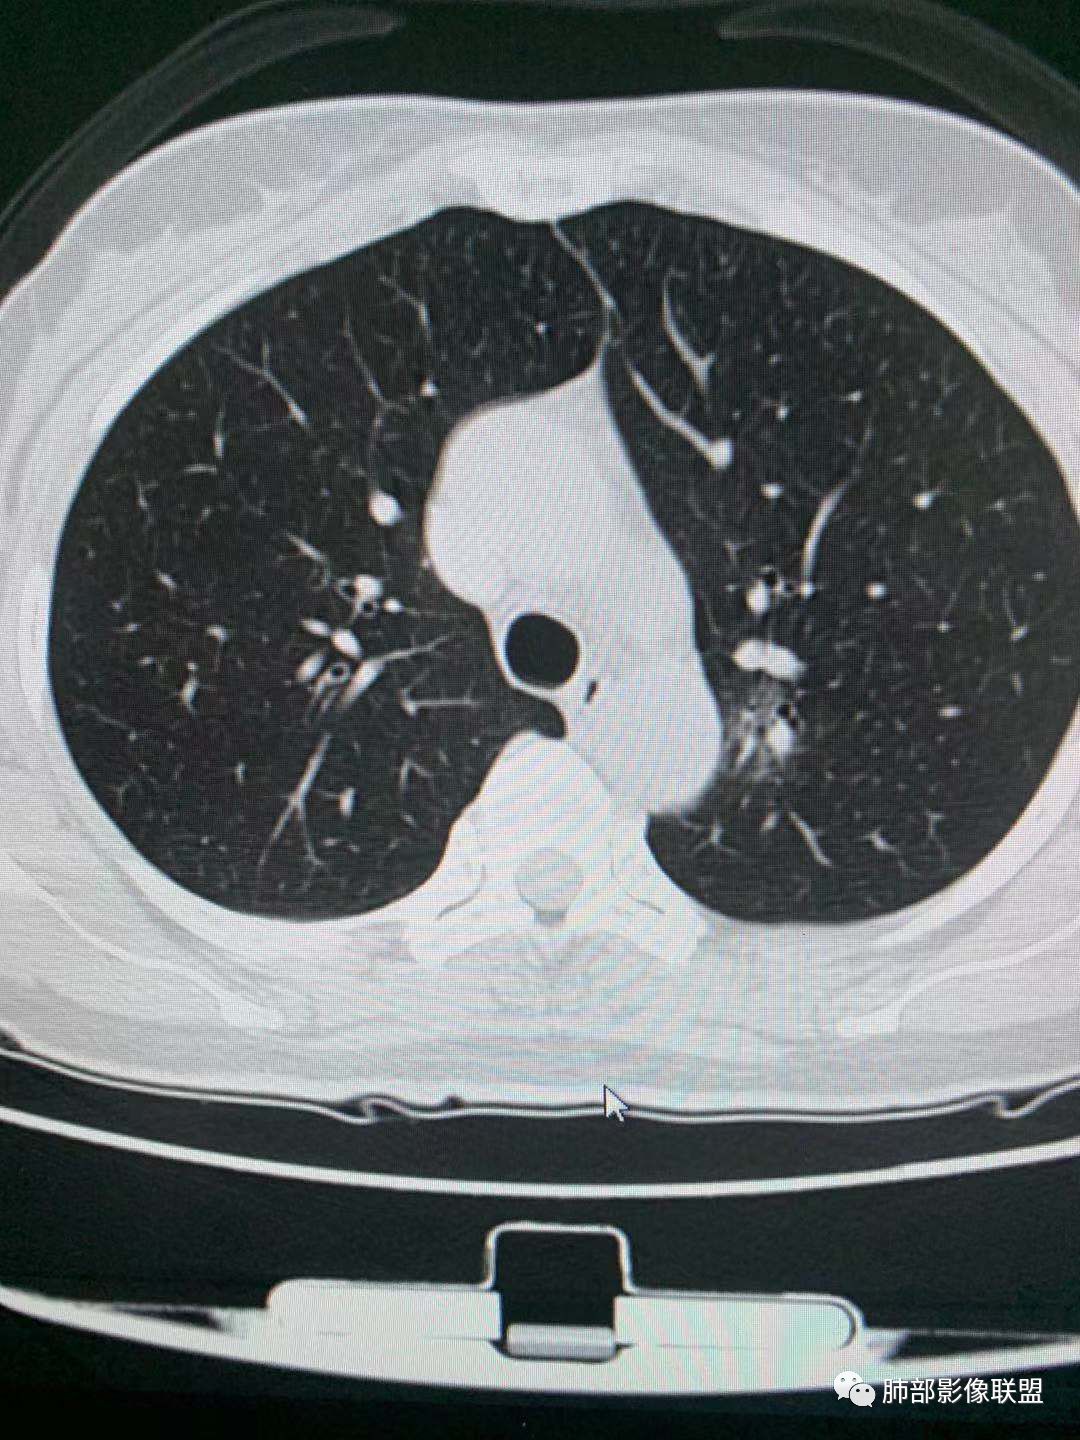

一.尖后段高密度大结节:

1.左肺上叶尖后段较大类圆形实性密度结节影,密度均匀,中等程度强化。

2.实性密度区边缘相当清楚,表面欠光整,偶见毛刺、棘突和旁出血管结构,未见典型的深分叶及邻近胸膜凹陷。

3.可疑支气管进入受阻。可惜缺乏连贯图像或冠矢状位以资判断。

4.病灶与胸膜之间有连线,邻近段支气管及肺血管整体后移,提示病灶还是有一定收缩性。

如上,单就这实性结节,硬化性肺细胞瘤(PSP)和腺癌似乎都能够解释,形态太规整了一些。

5.病灶周围见边界清楚的磨玻璃影,有点醒目,有点意外!

这是无论如何不能忽视的征象!

这点强烈提示,要么整个病灶恶性(腺癌),要么良性病灶旁滋生恶性病灶。

两年前左上肺的病灶什么位置,什么模样,是否相关?我们不得而知。